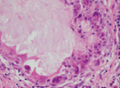

• 肺多发细支气管腺瘤恶变1例

肺多发细支气管腺瘤恶变1例

作者:刘洪杰,李永元,天津市第五中心医院 1.病例 女,69 岁,主因咳嗽、咳痰(白色黏痰)1 月余,于外院行胸部CT 平扫:左肺胸膜下多发结节及菜花状肿块,边界清晰,具有融合趋